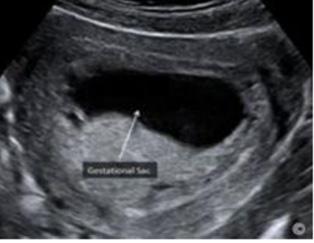

En la del I trimestre (10-14 semanas), se confirman la gestación, la edad gestacional de forma más precisa midiendo la longitud craneocaudal (LCC)

(ENAM EXTRA 2021), y la vitalidad del embrión (actividad cardiaca) (ENAM EXTRA 2020)

Figura 35. Pruebas invasivas Figura 36. Ecografía de I trimestre medición de la ICC